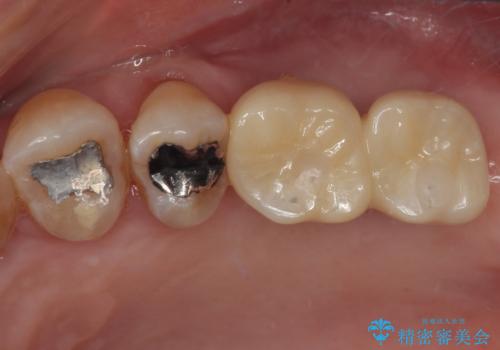

インプラントが待機期間に脱落することがありますが、一切のトラブルなく、最短期間で無事に治療を終えることができました。